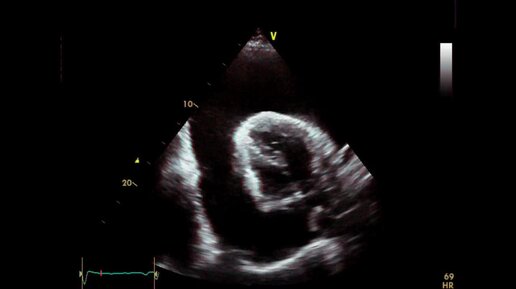

Тампонада сердца — это скопление жидкости вокруг сердечной мышцы, которое оказывает давление на орган. У людей с тампонадой сердца жидкость или кровь скапливаются между сердцем и сумкой (перикардом), которая окружает сердце. Перикард состоит из двух тонких слоев ткани, содержащих небольшое количество жидкости для предотвращения трения между слоями. Однако аномально высокий уровень жидкости оказывает давление на сердце и влияет на его способность должным образом перекачивать кровь по всему организму...

Тампонада сердца имеет высокий уровень смертности, поэтому требует быстрого реагирования и немедленной медицинской помощи. Прочтите статью до конца, чтобы узнать, как распознать недуг, спасти жизнь себе или близким и не допустить рецидива.  Что скрывается за страшным диагнозом? Тампонада сердца (лат. tamponade cordis, англ. cardiac tamponade) – это опасное для жизни состояние, при котором кровь или другая жидкость попадает в полость перикарда («сердечная сумка»). Жидкость сдавливает сердце и препятствует...